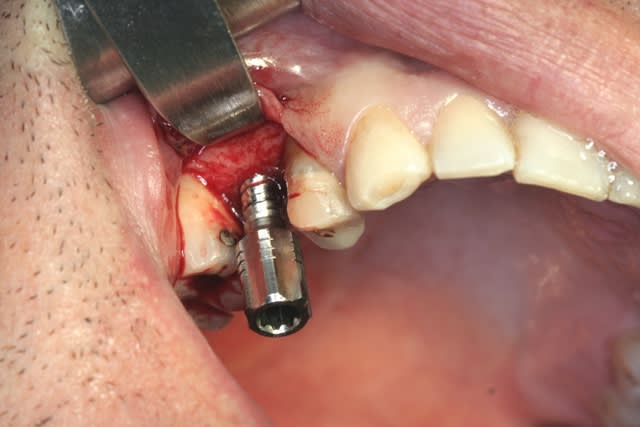

tiens...un ptit cas...

dans ce petit cas...j'ai commencé avec le kit MIS...et fini ma voie crestale avec le kit HBS...

ok, c'est un mini soulevé...mais bon , c'est un exemple...

juste une précision...premier foret 1.3mm sur 8mm...expansion pour mettre un implant de 4x10...

j'ai juste "léché" la préparation du site final avec le foret terminal du système...sur 8mm...avant d'insérer l'implant...stab primaire au top...blocage à 40 Ncm...